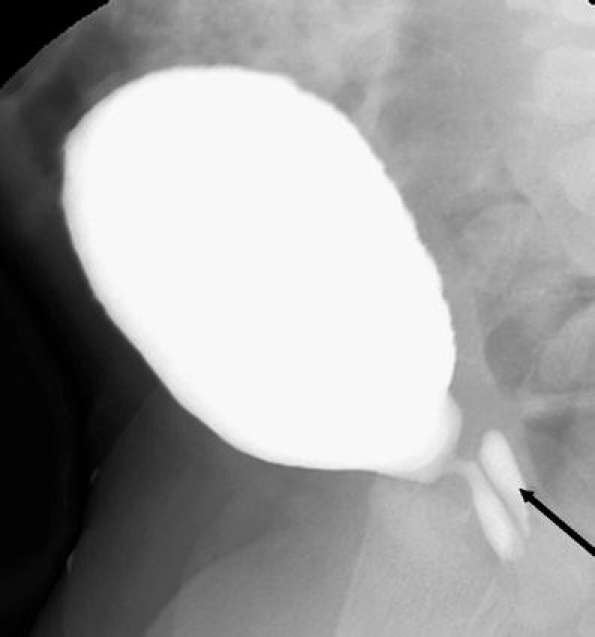

Fig. 10.

Congenital urethral stricture. A markedly dilated urethra is seen proximal to a congenital stricture in the bulbous urethra. Retrograde urethrography in this patient (not shown) demonstrated a focal narrowing at the bulbous urethra with a normal penile urethra. The site of obstruction is more distal than that seen with PUV